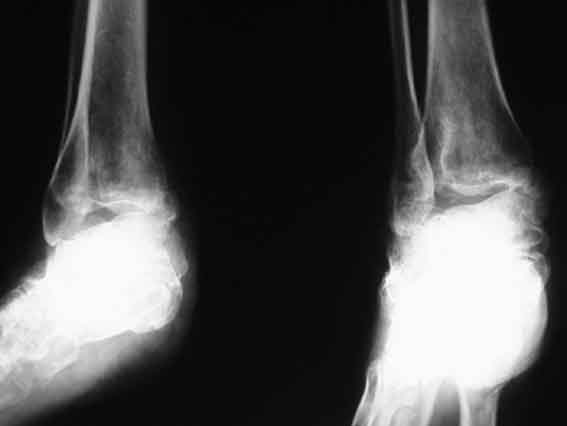

Застарелый вывих пяточной кости

Больная, 41 год, продавец, поступила в плановом порядке. Травма 1 год назад, вышла из двери второго этажа недостроенного дома с высоты 3 м. ДЗ. закр. перелом обеих лодыжек со смещением. Оскольчатый перелом пяточной кости. Вывих пяточной кости в подтаранном суставе кнаружи. При поступлении наложено вытяжение за пяточную кость 27.07 под в/в наркозом попытка устранения вывиха в подтаранном суставе (растягивался голеностопный сустав) безуспешна. Наложен гипс.

В последующем развился некроз кожного лоскута в области внутреней лодыжки 4х5 из-за натяжения кожи над внутренней лодыжкой. Консервативное лечение некроза кожи.Рана в области внутренней лодыжки зажила вторичным натяжением. В настоящее время Больная ходит на костылях с минимальной нагрузкой. При ходьбе беспокоят боли в стопе по подошве, в среднем отделе стопы, в области голеностопного сустава, переднего отдела стопы. Местно: имеется вальгусная деформация заднего отдела стопы, по внутренней поверхности стопы рубец - результат заживления раны вторичным натяжением, при пальпации резкая болезненность по подошвенно-внутренней поверхности стопы, движения в подтаранном суставе отсутствуют, при попытке их совершить появляется боль в проекции подтаранного сустава, сгибание разгибание в голеностопном суставе сохранены, болезненность появляется в крайних положениях сгибания-разгибания, имеются пронационные супинационные движения в голеностопном суставе. ДЗ Сросшийся со смещением перелом обеих лодыжек, подвывих книзу, сросшийся со смещением перелом пяточной кости вывих пяточной кости кнаружи. Коллеги, поделитесь мнением, что делать в такой ситуации? Снимок 1

Снимок 2